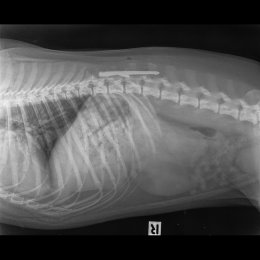

Radiographie Ventro Dorsale Et Laterale D Un Chat Avec Asthme Pneumonie Changements Bronchiques Et Alveolaires Importants Metastases De La Miliaria Possibles Photo Stock Alamy